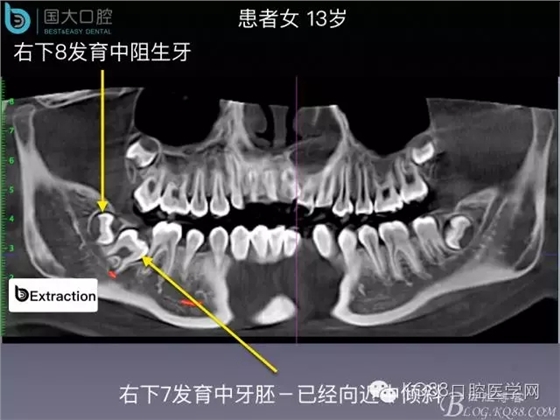

阻生牙的預(yù)防性拔除